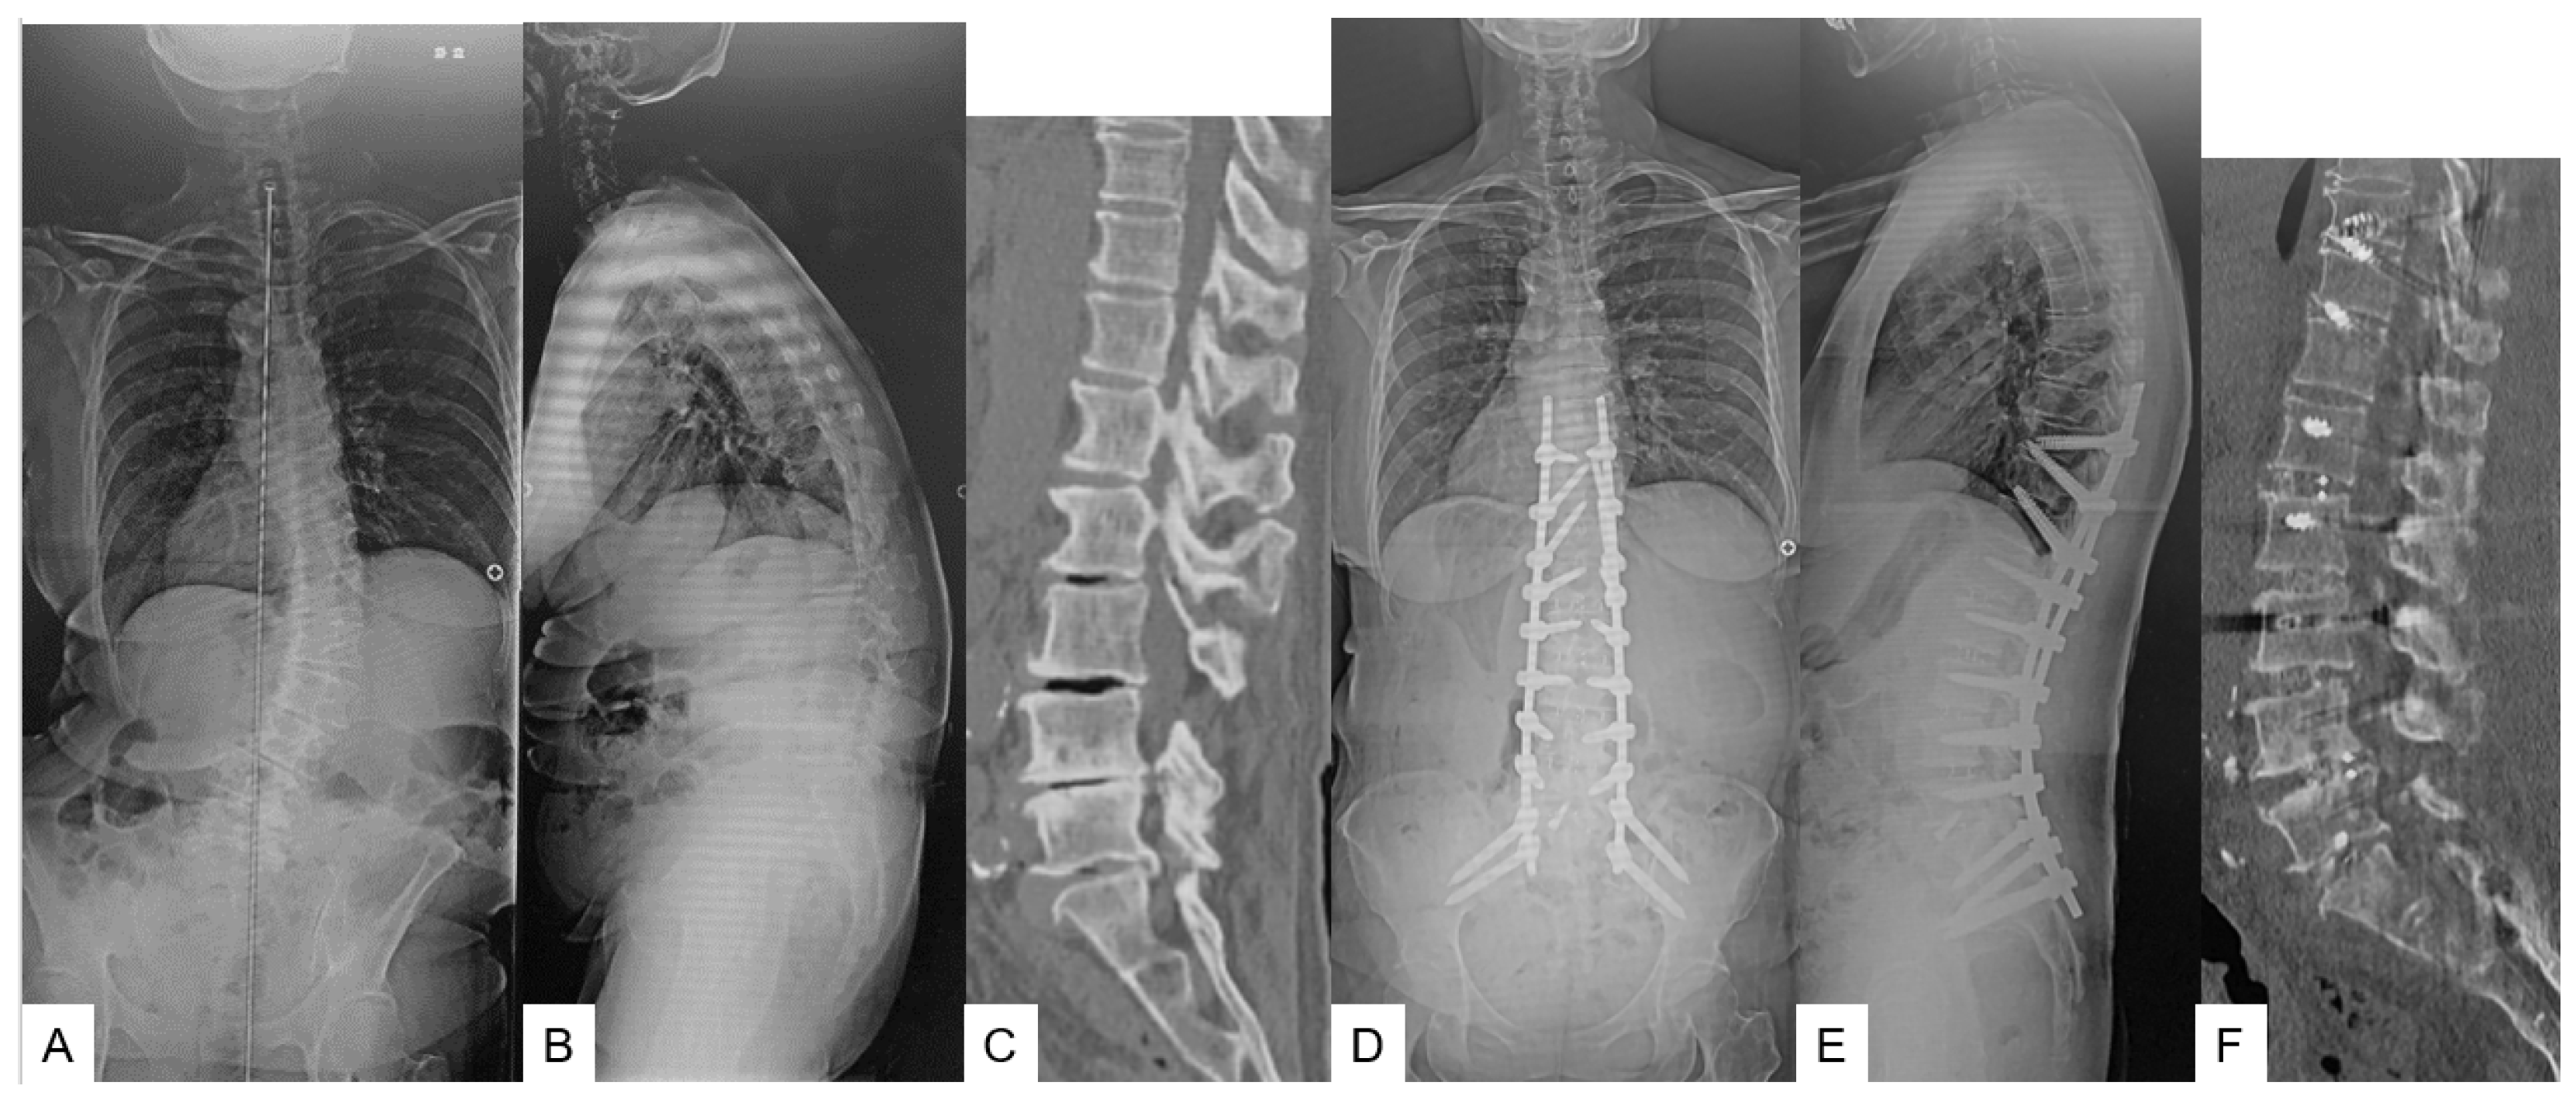

61-year-old female, adult spinal deformity, OLIF L1-S1 and T10-SAI. (A) Preoperative posteroanterior radiogram; (B) Preoperative lateral radiogram; Lateral radiogram showed severe sagittal malalignment; SVA of 181 mm, PT of 49°, PI-LL of 42°. (C) Preoperative CT. L5-S1 angle was 7.1°; (D) Postoperative posteroanterior radiogram; (E) Postoperative lateral radiogram. Lateral radiogram showed good sagittal malalignment; SVA of 5 mm, PT of 14°, PI-LL of 2°; (F) Postoperative CT. L5-S1 angle was 19.6°.

2.1.2. Secondary Surgery (T10-SAI in Group O or T10-SAI + TLIF51 in Group T) (Figure 1)